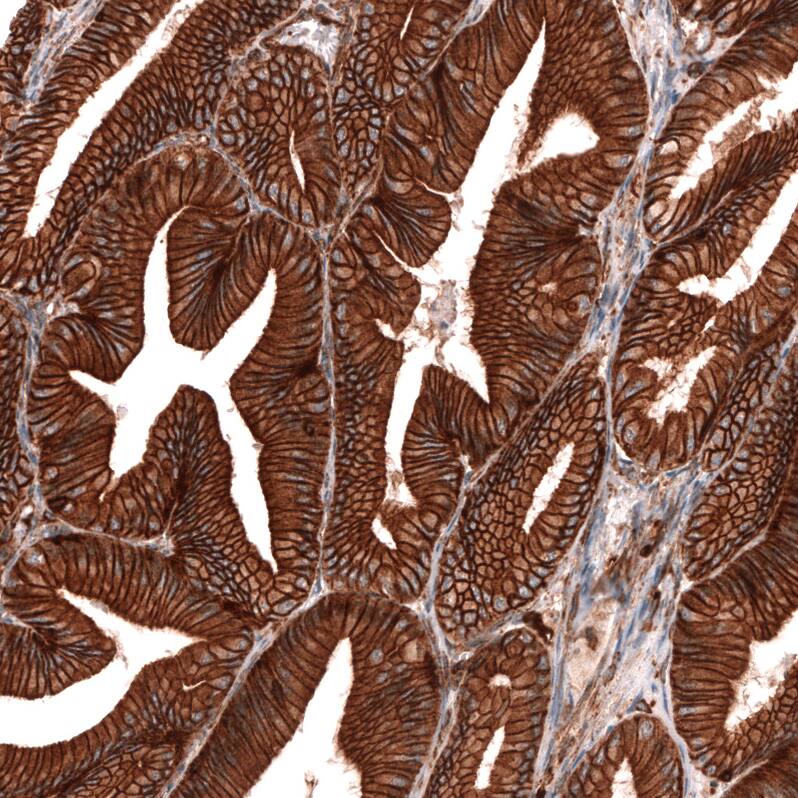

Immunohistochemistry-Paraffin: IGFBP-2 Antibody (CL13563) [NBP3-24568]

Staining of human stomach shows strong membranous positivity in glandular cells.